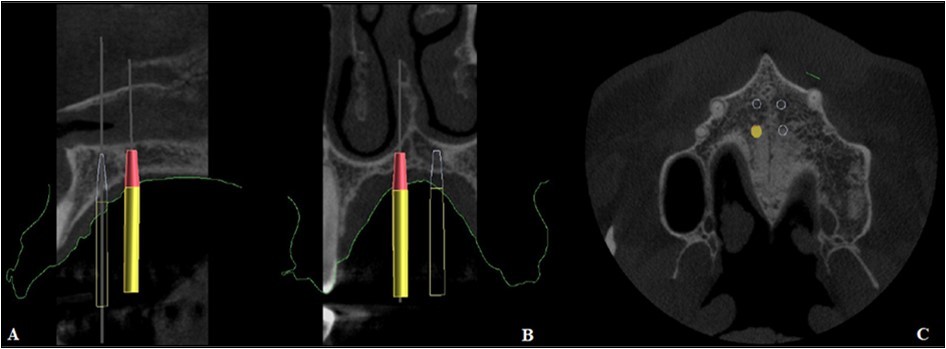

The precise position and angulation of the mini-implants is replicated by 4 cylindrical metallic guides taking into consideration the following parameters: bone thickness, soft tissue thickness and anatomical surrounding structures. The most appropriate site for the placement of mini-implants is: 3 mm lateral to the suture in the first premolar region. (Figure 3,Figure 4)

Figure 4.Positioning of the mini-implants on CBCT, A. Sagittal section, B. Coronal section, C. Axial section